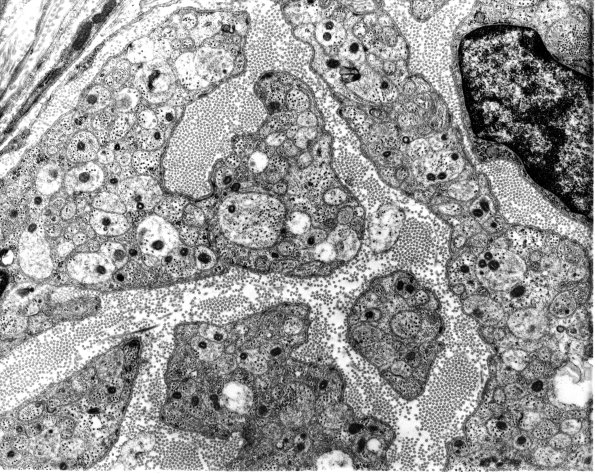

Washington University Experience | PERIPHERAL NEUROPATHY | 5 AXONAL REGENERATION | 1A3 Axons, regeneration (IV-236 CR3-3) Rat sciatic EM 1

1A3,4 Tiny axonal sprouts are often located within the same Schwann cell trough (arrowhead, 1A4) an appearance which is not seen in normal adult nerves. (electron micrographs)